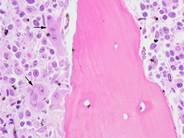

Higher power view of the same marrow biopsy reveals a large cell infiltrate with prominent nucleoli and abundant cytoplasm. Both immunoblastic and plasmablastic features are present.